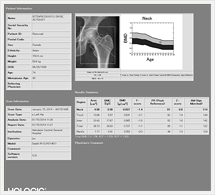

骨密度測定検査(DXA)

骨密度測定検査とは

体の中の腰椎等の骨密度を弱いX線を使用して非侵襲に測定し、骨粗鬆症の診断や、その経過観察に有用な情報をもたらす検査法です。

検査所要時間は10分程度で、検査による痛みはございませんので安心して検査をお受け下さい。

画像紹介